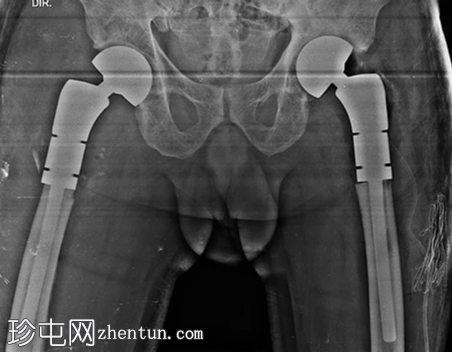

X线片

术后即刻复查X线片。

双侧近端股骨置换术(双极型)。

假体柄采用骨水泥固定。

假体位置良好。